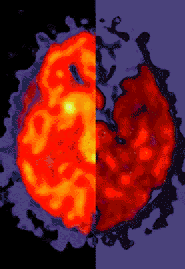

There are many terrible after effects to Ecstasy...aka adam, x, xtc, clarity, wonder drug, E, essence, and love drug. It usually comes in tablets or capsules that are 100-128 mgs a dose. Ecstasy is a drug that stimulates the nerves in the brain and causes a excessive amount of serotnin to be released. That, in turn, causes brain damage because the nerves are over worked. Serotonin is a vital part of the brain's functions because it regulates eating, sleeping and behaviour patterns. Drinking too much water AFTER the dose of ecstasy can be very dangerous because the body contains a high amount of vasopressin. This hormone causes the body to retain more water, diluting the sodium and other salts in the blood. This can cause the brain to swellm, thus damaging the brain itself and the surrounding nerve tissues. E causes damage to a specific part of the brain that is vital to thought and memory. This drug belongs to a family of drugs called "entactogens", ecstasy is also a designer drug, which means it has been changed and has many variables to changing it to a different chemical structure to make it a totally different drug which can cause similar or totally different effects.